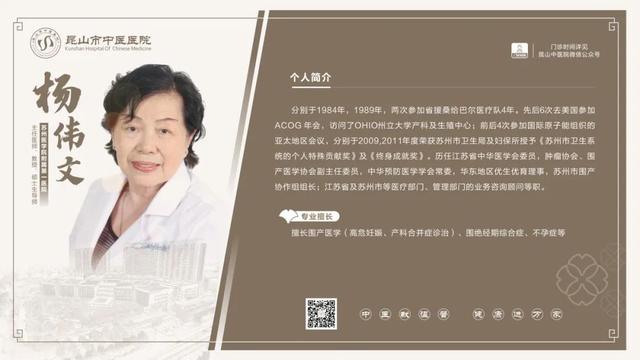

6��23��-6��29�������dz���ר�ҽ���